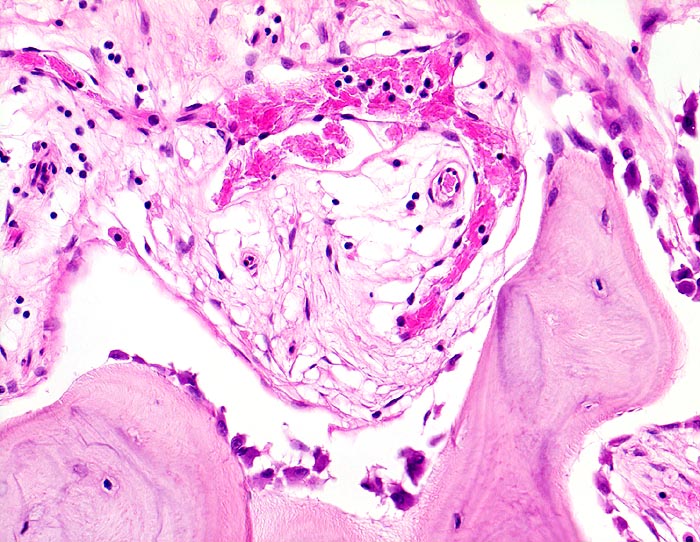

An den betroffenen Stellen ist sowohl der Knochenabbau als auch der Knochenanbau gesteigert. Die Osteoklasten sind auffallend gross und enthalten sehr viele Kerne (> 3518). Die aktivierten Osteoblasten produzieren verdickte und grob geflochtene Spongiosabälkchen. Der neugebildete Knochen ist strukturell und morphologisch abnorm und schlecht mineralisiert. Der Knochen wird dadurch weich und anfällig auf Frakturen oder Deformation unter Belastung (nach vorne gebogene Säbelscheidentibia). Das Knochenmark wird ersetzt durch fibrovaskuläres lockeres Stroma, welches an Granulationsgewebe erinnert. Mikroskopisch werden eine osteolytische Initialphase, eine Umbauphase mit verstärkter Knochenneubildung und eine sklerosierende Stabilisationsphase mit strukturellem Umbau und Spongiosierung der Kortikalis (verbreiterte spongiosaartige Kortikalis) unterschieden.

• Lockere Markfibrose.